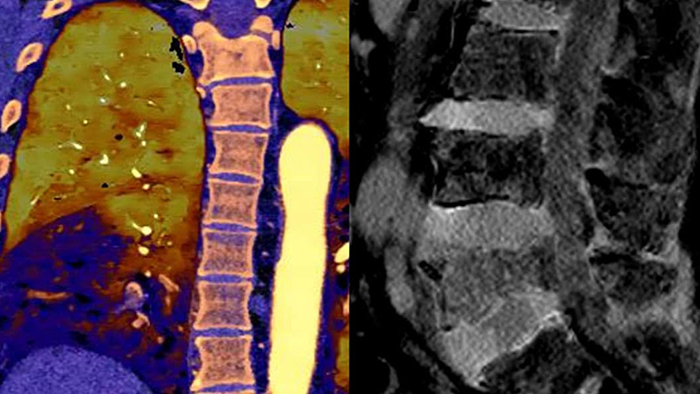

Грудная клетка, исследование на перикардиальный выпот